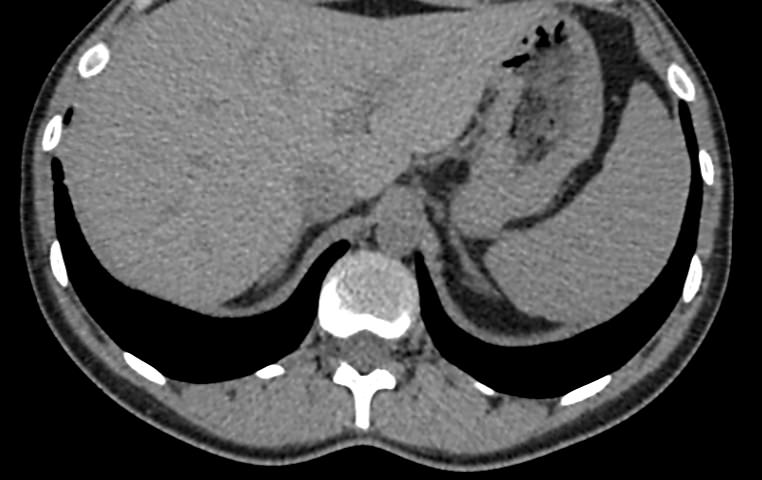

Мультиспиральная компьютерная томография селезенки – высокоинформативный инструментальный метод исследования, основанный на использовании рентгеновского излучения и позволяющий детально визуализировать паренхиму селезенки, состояние близлежащих органов и тканей, питающих ее кровеносных сосудов и лимфоузлов.

МСКТ селезенки проводится как с использованием контраста, так и без него. Контрастирование применяется для выявления патологических очагов, которые могут быть не видны при нативном исследовании. Для этого внутривенно вводится контрастный препарат, содержащий йод и накапливающийся в патологических очагах опухолевой и воспалительной природы.

Нативная КТ (бесконтрастное исследование селезенки) показывает структуру органа достаточно однородно, без выявления незначительных изменений. Для большей информативности делают КТ селезенки с применением контрастных веществ.

На томограмме можно увидеть:

- нарушение целостности селезенки;

- кисты и крупные опухоли;

- кальцинаты;

- травматические и посттравматические изменения селезенки

- кровоизлияния внутрь брюшной полости

- отклонения от нормальных размеров.

- дополнительные дольки селезенки.